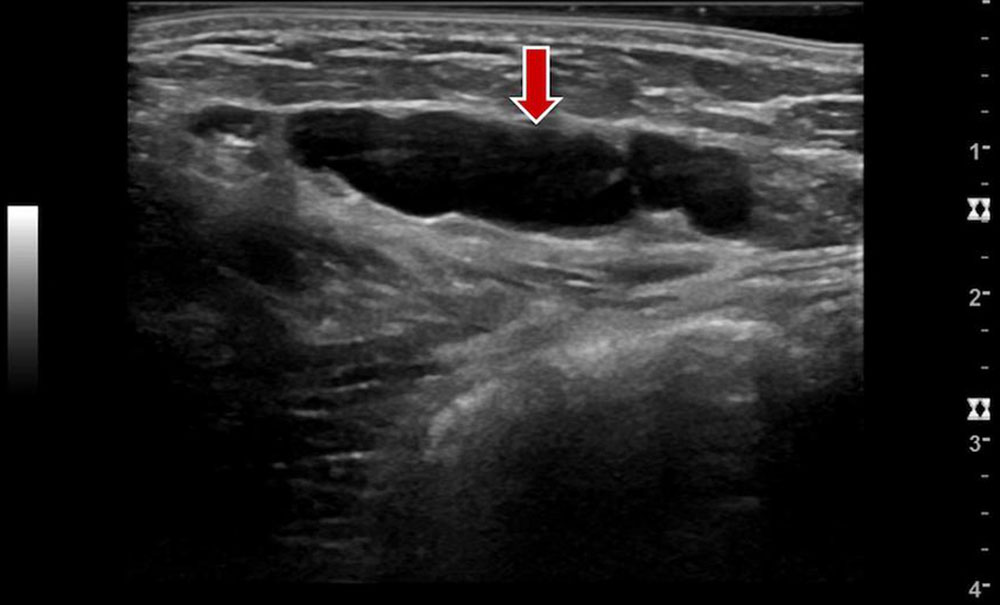

• Venous malformation: In B-mode images, venous malformations are shown as tubular and sponge-like echo-free spaces. Typically, these spaces are surrounded by echogenic fatty tissue. In the absence of thrombi or phleboliths within the venous malformation, the venous malformation is usually easily compressible with the ultrasound probe. Color-coded duplex sonography (CCDS) does not detect increased flow or shows no blood flow within the venous malformation, unlike in fast-flow malformations. The patency of the deep venous system can additionally be assessed by compression ultrasound before and after invasive therapy.